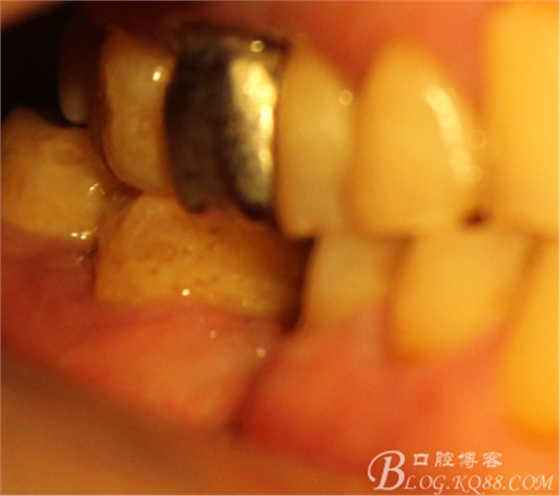

因為左上做過種植,口內(nèi)見

C6頰側(cè)骨缺損凹陷,對合金屬全冠,